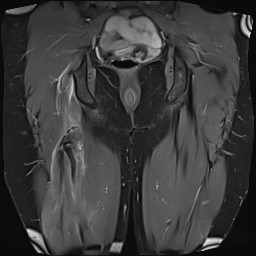

MRI

Complete / retracted tears

Proximal hamstring tear on right (red circle), normal insertion on tuberosity on left (blue circle)

Proximal hamstring avulsion on right - red circle is retracted hamstring tendon, blue circle is normal insertion on left

Proximal hamstring tear on right (red circle), normal insertion on left (blue circle)

Proximal hamstring avulsion, with tendon floating in hematoma / seroma